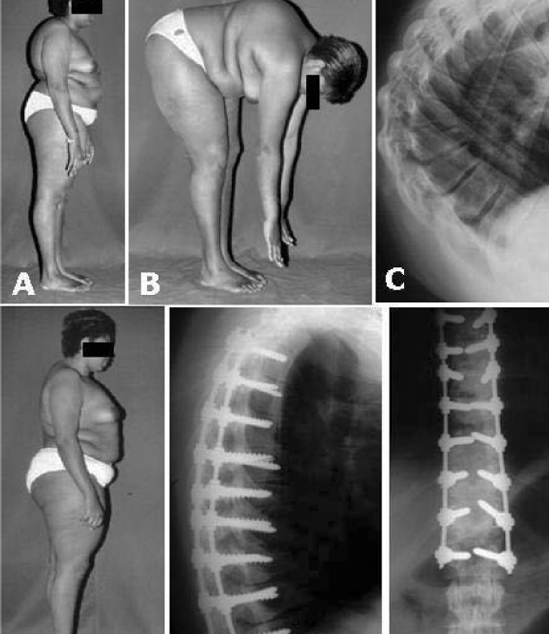

Quais são as indicações para cirurgia na Doença de Scheuermann?

A cirurgia é indicada para cifose superior a 75°, cifose progressiva apesar do uso de colete ou cifose significativa e dolorosa sem alívio por métodos conservadores.

Quais técnicas cirúrgicas são utilizadas?

As técnicas cirúrgicas podem incluir alongamento da coluna anterior, encurtamento e estabilização da coluna posterior, e cuidado com a área watershed.